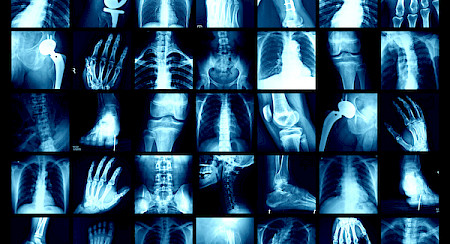

La radiologie standardou radiographie est l’étude des articulations au niveau osseux. Examen de première intention, la radiographie permet de visualiser des parties spécifiques du corps humain (os et certains organes) et décèle les fractures et l’arthrose. Elle utilise des rayons X (onde à fréquence élevée), qui - en traversant le corps - sont atténués par les différentes structures (p. ex. les os, les tissus mous). Sur la radiographie, les os apparaîtront en blanc, tandis que les tissus mous s’afficheront dans des tons gris.